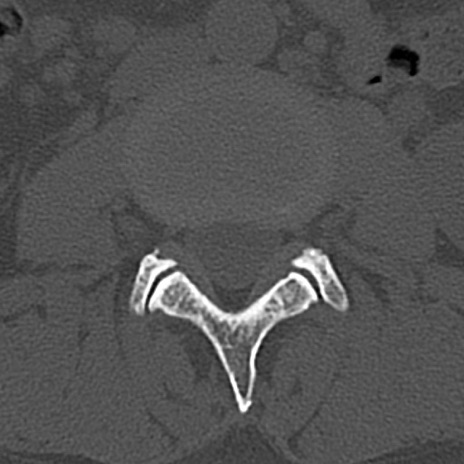

腰椎CT

横断像と矢状断像